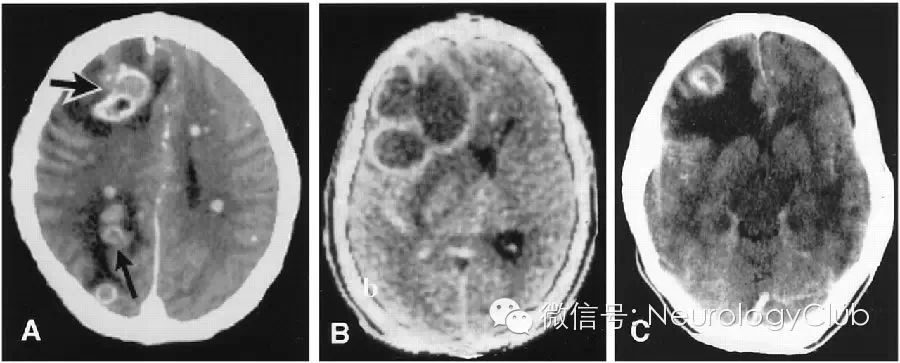

2.感染

7bba9c72059bb7d9495c2a7c2c3ba814.jpg

(引自:Masdeu JC, et al. Open-ring imaging sign: highly specific for atypical brain demyelination.Neurology. 2000 Apr 11;54(7):1427-33.)